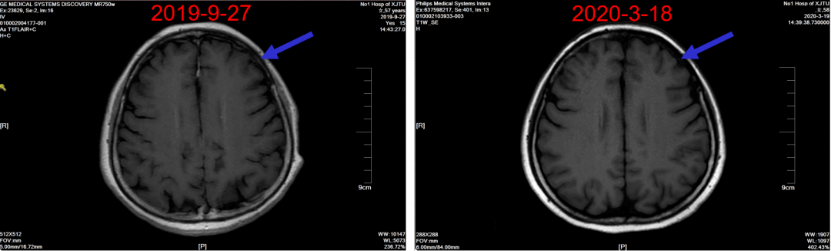

图6:一线治疗期间随访颅脑CT

图7:一线维持治疗期间随访颅脑CT